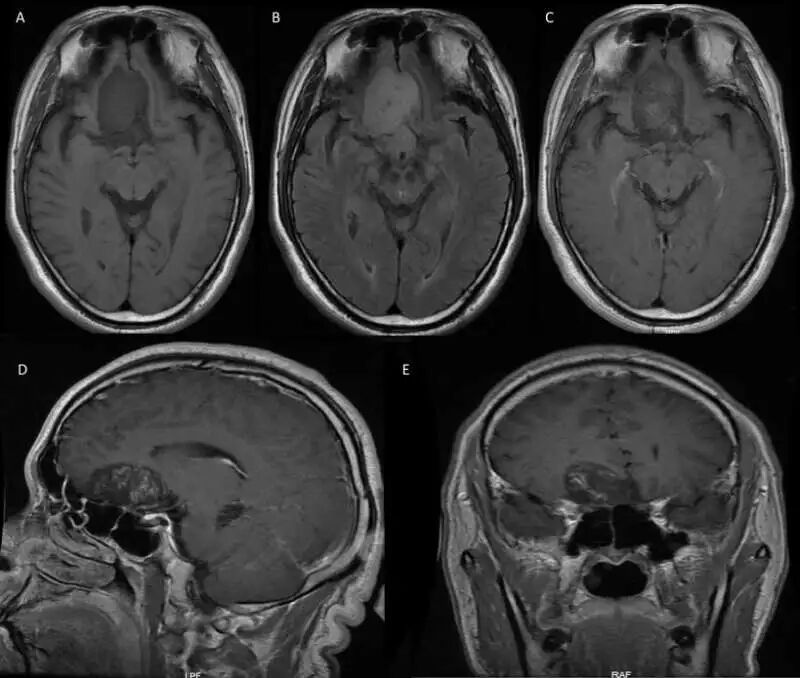

入院后完善相关检查,头颅增强MR提示前颅窝底偏右侧类圆形异常信号影,T1低信号,T2FLAIR高信号,增强内见絮状强化。考虑良性肿瘤可能性大,恶性肿瘤待排(图1)。

图1. 头颅增强MR见前颅窝底偏右侧类圆形异常信号影,T1低信号(A),T2 FLAIR高信号(B),边界清晰,中线结构略左移,增强后内见絮状强化(C-E),大小约37mm×43mm×27mm。